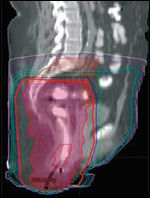

Sagittal image from conventional 3-dimensional radiation planning.FIGURE 5

Sagittal image from intensity- modulated radiation therapy planning in the same patient.FIGURE 6

RTOG 05-29 is a prospective phase II efficacy trial utilizing IMRT in the treatment of anal canal cancer.[39] All patients received concurrent 5FU and MMC. In this study, IMRT was delivered by “dose painting,” in which different target volumes are treated concurrently but different-sized radiation fractions are used for different target structures, which is achievable with IMRT. The doses prescribed to elective nodal areas depended on the stage of disease, and the total dose to gross disease ranged from 50.4 to 54 Gy. As an example, the patient depicted in Figures 2-9 with T2N2M0 disease might have received 1.5 Gy/day (to a total of 45 Gy) to the uninvolved (elective) inguinal and upper pelvic regions, 1.68 Gy/day (to a total of 50.4 Gy) to an involved right pelvic lymph node (which measured ≤ 3 cm), and 1.8 Gy/day (to a total of 54 Gy) to the gross anal canal tumor.